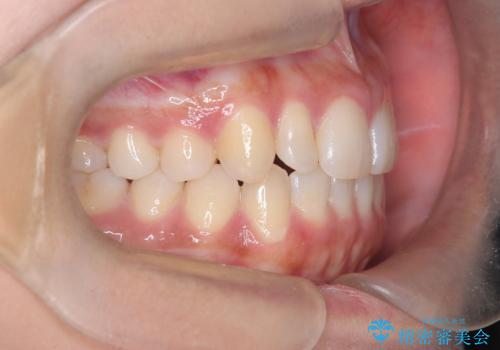

反対咬合と前歯のガタガタを非抜歯で改善

- 患者様は、上下の前歯のガタガタと反対咬合(下の歯が上の歯より前に出ている状態)を主訴として来院されました。診断の結果、抜歯を行わずに治療を進めるため、臼歯を遠心移動させてスペースを作り、IPR(インタープロキシマルリダクション)で歯間を調整する治療計画を立てました。インビザラインを使用して、透明で目立たない矯正装置により、歯列を整えながら噛み合わせも改善することを目標としました。

非抜歯での治療では、限られたスペースの中で効率的に歯を動かす必要があります。本症例では、臼歯を後方に移動させる遠心移動を行い、歯列のガタガタを改善しました。また、IPRを適切に行うことでスペースを確保し、歯根や歯肉への負担を最小限に抑えながら治療を進めました。インビザラインを使用することで、治療中も目立ちにくく、患者様の日常生活への影響を軽減しました。結果として、抜歯を行わずに美しい歯並びと自然な噛み合わせを実現し、患者様には大変満足していただけました。